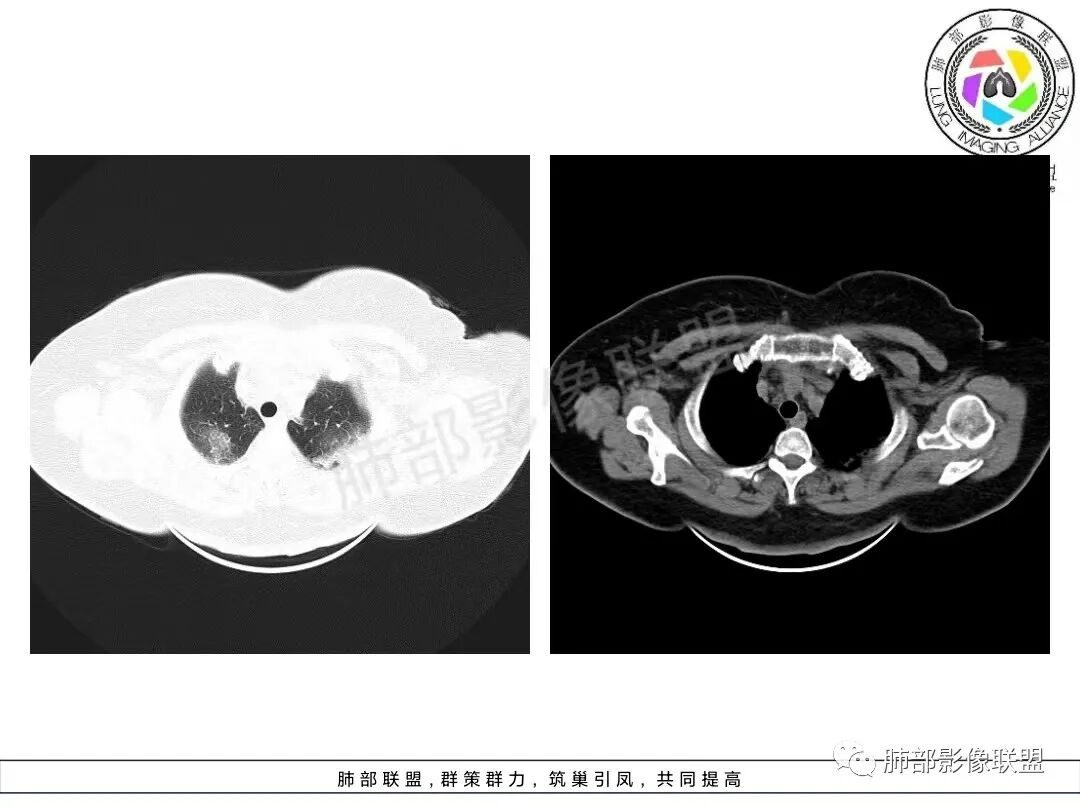

两肺沿胸膜下分布为主,大片、斑片状不均质实变,肺窗>纵隔窗,提示累及肺实质和间质,实变内充气支气管征空洞几乎不见,边缘收缩凹陷,部分平直,肺体积整体未见缩小。临床血氧降低,白细胞升高,考虑OP,COP,鉴别隐球菌,粘液腺癌!

老年女性,咳嗽、咳黄白痰,无发热,化验炎性指标高,右肺胸膜下实变,其内支气管充气、扩张,周围索条,左肺胸膜下多发结节及斑片实变,胸膜下线影,右侧少量胸水,考虑机化性肺炎,鉴别隐球菌、粘液腺癌

双肺胸膜下多发实变,边界不清,较大病变长轴与胸膜平行,近端可见充气支气管征,部分病灶内坏死边界清,胸膜下有多发相类似病灶,综合考虑首选隐球菌,其次0P尚不除外

双肺胸膜下多发斑片及大片实变影,边缘清晰,长轴平行于胸膜,部分病灶呈细网格状,右侧胸膜增厚,右侧叶间胸膜增厚,血糖高,感染指标高,考虑OP,鉴别隐球菌

双肺胸膜下大片、斑片影,密度不均,边缘模糊,周围索条,右侧少量胸水,考虑机化性肺炎,鉴别隐球菌、粘液腺癌

2、影像特点:双肺胸膜下为主、多发斑片影、结节样实变影及磨玻璃样密度影,大部分病灶边缘平直、边界清,磨玻璃密度病灶内可见细网格影,部分病灶内可见支气管扩张表现,部分支气管直达远端,部分中断于病灶中部。部分病灶有侧向融合趋势。